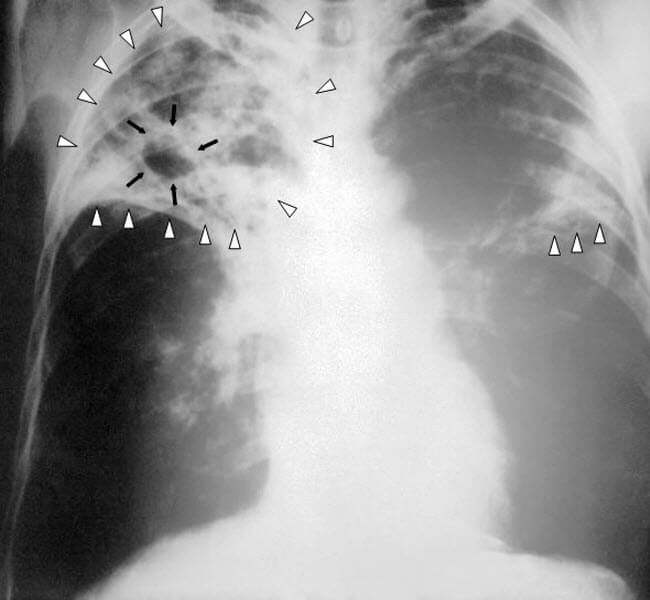

Фахівці розповіли про найпоширеніші міфи про туберкульоз. Багато з них виявилися неправдою і були спростовані експертами.